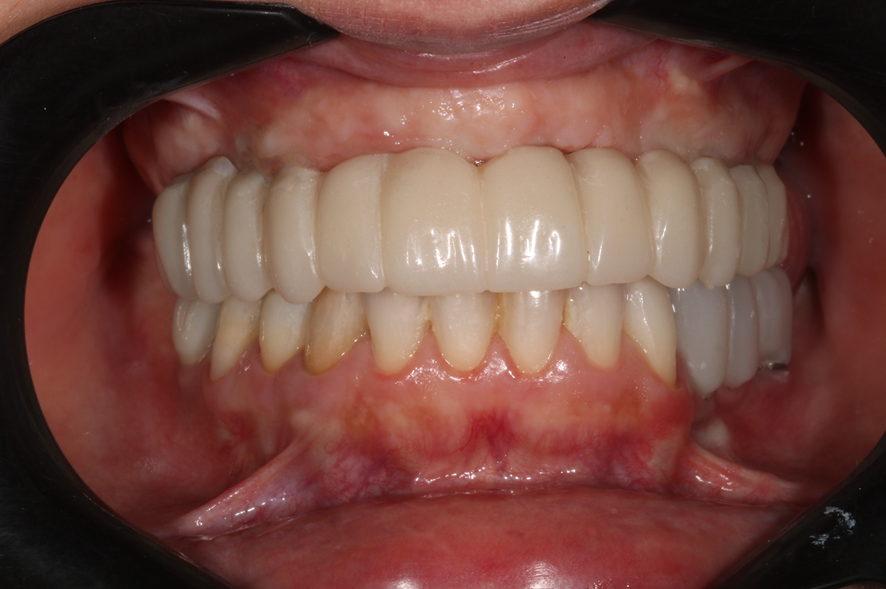

Instalação da prótese em PMMA.